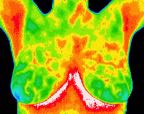

These are thermograms of breasts captured by digital infrared thermal imaging.

1- A complete normal study of the breasts.jpg

A complete normal study of the breasts